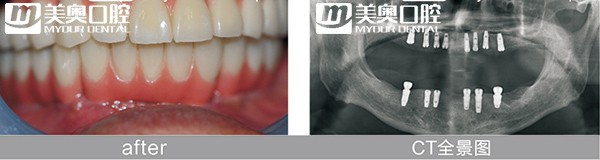

就在上个月,全口缺牙的63岁的徐先生在美奥口腔当天种牙,通过即拔即种即刻修复技术,拔除了2颗残根,同时种上种植体,安装牙冠,1天内就从缺牙到有牙;时隔一个星期,82岁的孟女士植人4颗植体,通过All-on-4即刻负重,当天戴上了整排牙,吃起了苹果;而上周末70岁的于先生因为需要种植6颗牙,计算了所有的费用,感觉有点负担,但因为购买了3个百元种牙福袋,获得了3颗免费的种植体,费用一下子减少了一半。

而像孟女士这样半口、全口的缺牙者,采取的是All-on-4即刻负重,半口缺牙只需在牙槽骨植入4颗植体,在当天戴上整排牙齿,恢复咀嚼力。将原本长达半年到1年的修复时期缩短到1天。不仅在戴牙当天可以吃饭,随着时间的推移,患者感到牙齿越来越有力。

而像All-on-4这样特殊的半口、全口种植牙,在种植体的基台上安装“拱形连桥”牙冠,这样整个种植牙的受力就呈现出“拱形”的特征,即一点受力会均匀地分布到整体,这在建筑学上是最为稳固的形状。这种稳固的结构也使在植入种植体的当天,就可以安装牙冠恢复美观和咀嚼。